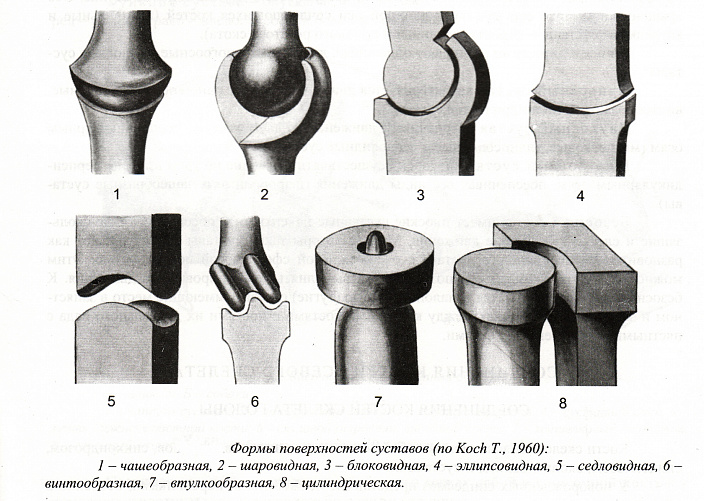

Классификация по функциям и траектории движений основана на форме суставных поверхностей. Исходя из этого критерия, выделяют следующие группы:

- Одноосные суставы: цилиндрический, блоковидный и винтообразный. Цилиндрический сустав способен выполнять вращательные движения. По этому принципу устроено сочленение между первым и вторым шейными позвонками. Блоковидный сустав позволяет выполнять движения только по одной оси, например, вперёд/назад или вправо/влево. Разновидностью таких сочленений являются винтообразные суставы, в которых траектория движений выполняется немного косо, образуя своеобразный винт.

- Двухосные суставы: эллипсовидный, седловидный, мыщелковый. Эллипсовидный сустав образован суставными поверхностями, одна из которых имеет выпуклую форму, а другая — вогнутую. Благодаря этому в сочленениях данного типа может поддерживаться движение вокруг двух взаимно перпендикулярных осей. Седловидный сустав в организме человека только один — запястно-пястный. Траектория движений в нём охватывает вращение, включая раскачивание из стороны в сторону и вперёд/назад. Мыщелковые суставы способны поддерживать аналогичную подвижность благодаря эллипсовидному отростку (мыщелку) на одной из костей и подходящей по размеру впадине на другой суставной поверхности.

- Многоосные суставы: шаровидный, чашеобразный, плоский. Шаровидные суставы — одни из самых функциональных, поскольку подразумевают наиболее широкий диапазон движений. Чашеобразные сочленения являются чуть менее подвижной версией шаровидных. А плоские суставы, наоборот, отличаются примитивным строением и минимальным объёмом движений.